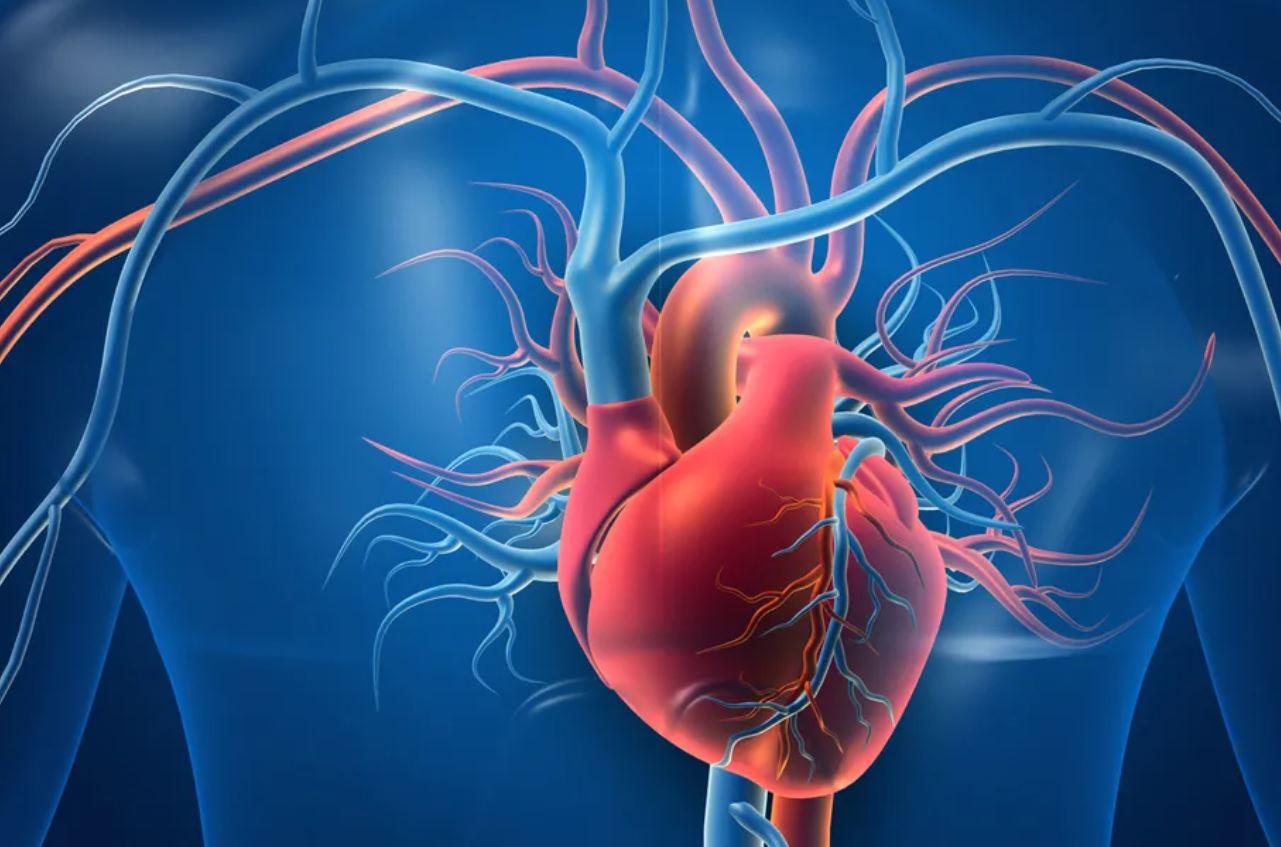

U svojoj osnovi, srce je mišić – ali ne bilo kakav. Njegova struktura je prilagođena neprekidnom radu bez pauze. Podijeljeno je na četiri šupljine: dvije pretkomore (atriji) i dvije komore (ventrikuli). Ova organizacija omogućava precizno usmjeravanje krvi kroz tijelo. Desna strana srca prima krv siromašnu kisikom i šalje je u pluća, dok lijeva strana prima krv bogatu kisikom i pumpa je prema svim organima i tkivima. Ovaj savršeno koordiniran proces odvija se hiljadama puta dnevno, bez našeg svjesnog učešća.

Krvotok koji srce pokreće predstavlja mrežu dugu desetine hiljada kilometara. Kroz arterije, vene i kapilare, krv prenosi kisik, hranjive materije, hormone i druge važne supstance. Bez ovog sistema, nijedna ćelija ne bi mogla opstati. Srce, dakle, nije samo centralni organ, već i ključna karika u održavanju života svake pojedinačne ćelije u tijelu.